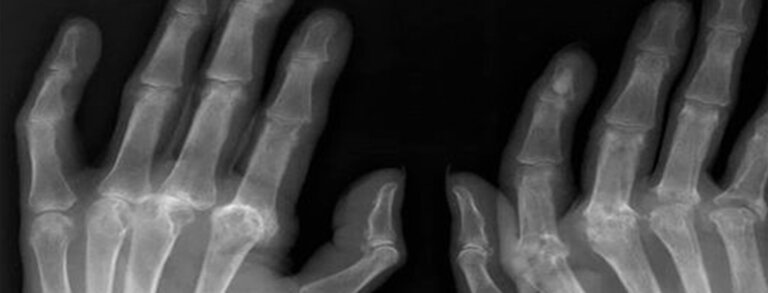

Savremeni pristupi liječenju reumatoidnog artritisa

Dr Milan Bogojević Klinički centar Crne Gore Reumatoidni artritis (RA) predstavlja jednu od najčešćih i najznačajnijih hroničnih upalnih reumatskih bolesti,...

Liječenje reumatoloških pacijenata biološkom terapijom

Mr sc. dr Ana Bulatović, internista reumatolog Načelnica Odjeljenja za reumatologiju KCCG Prva velika medicinska otkrića su počela sa pronalaskom...